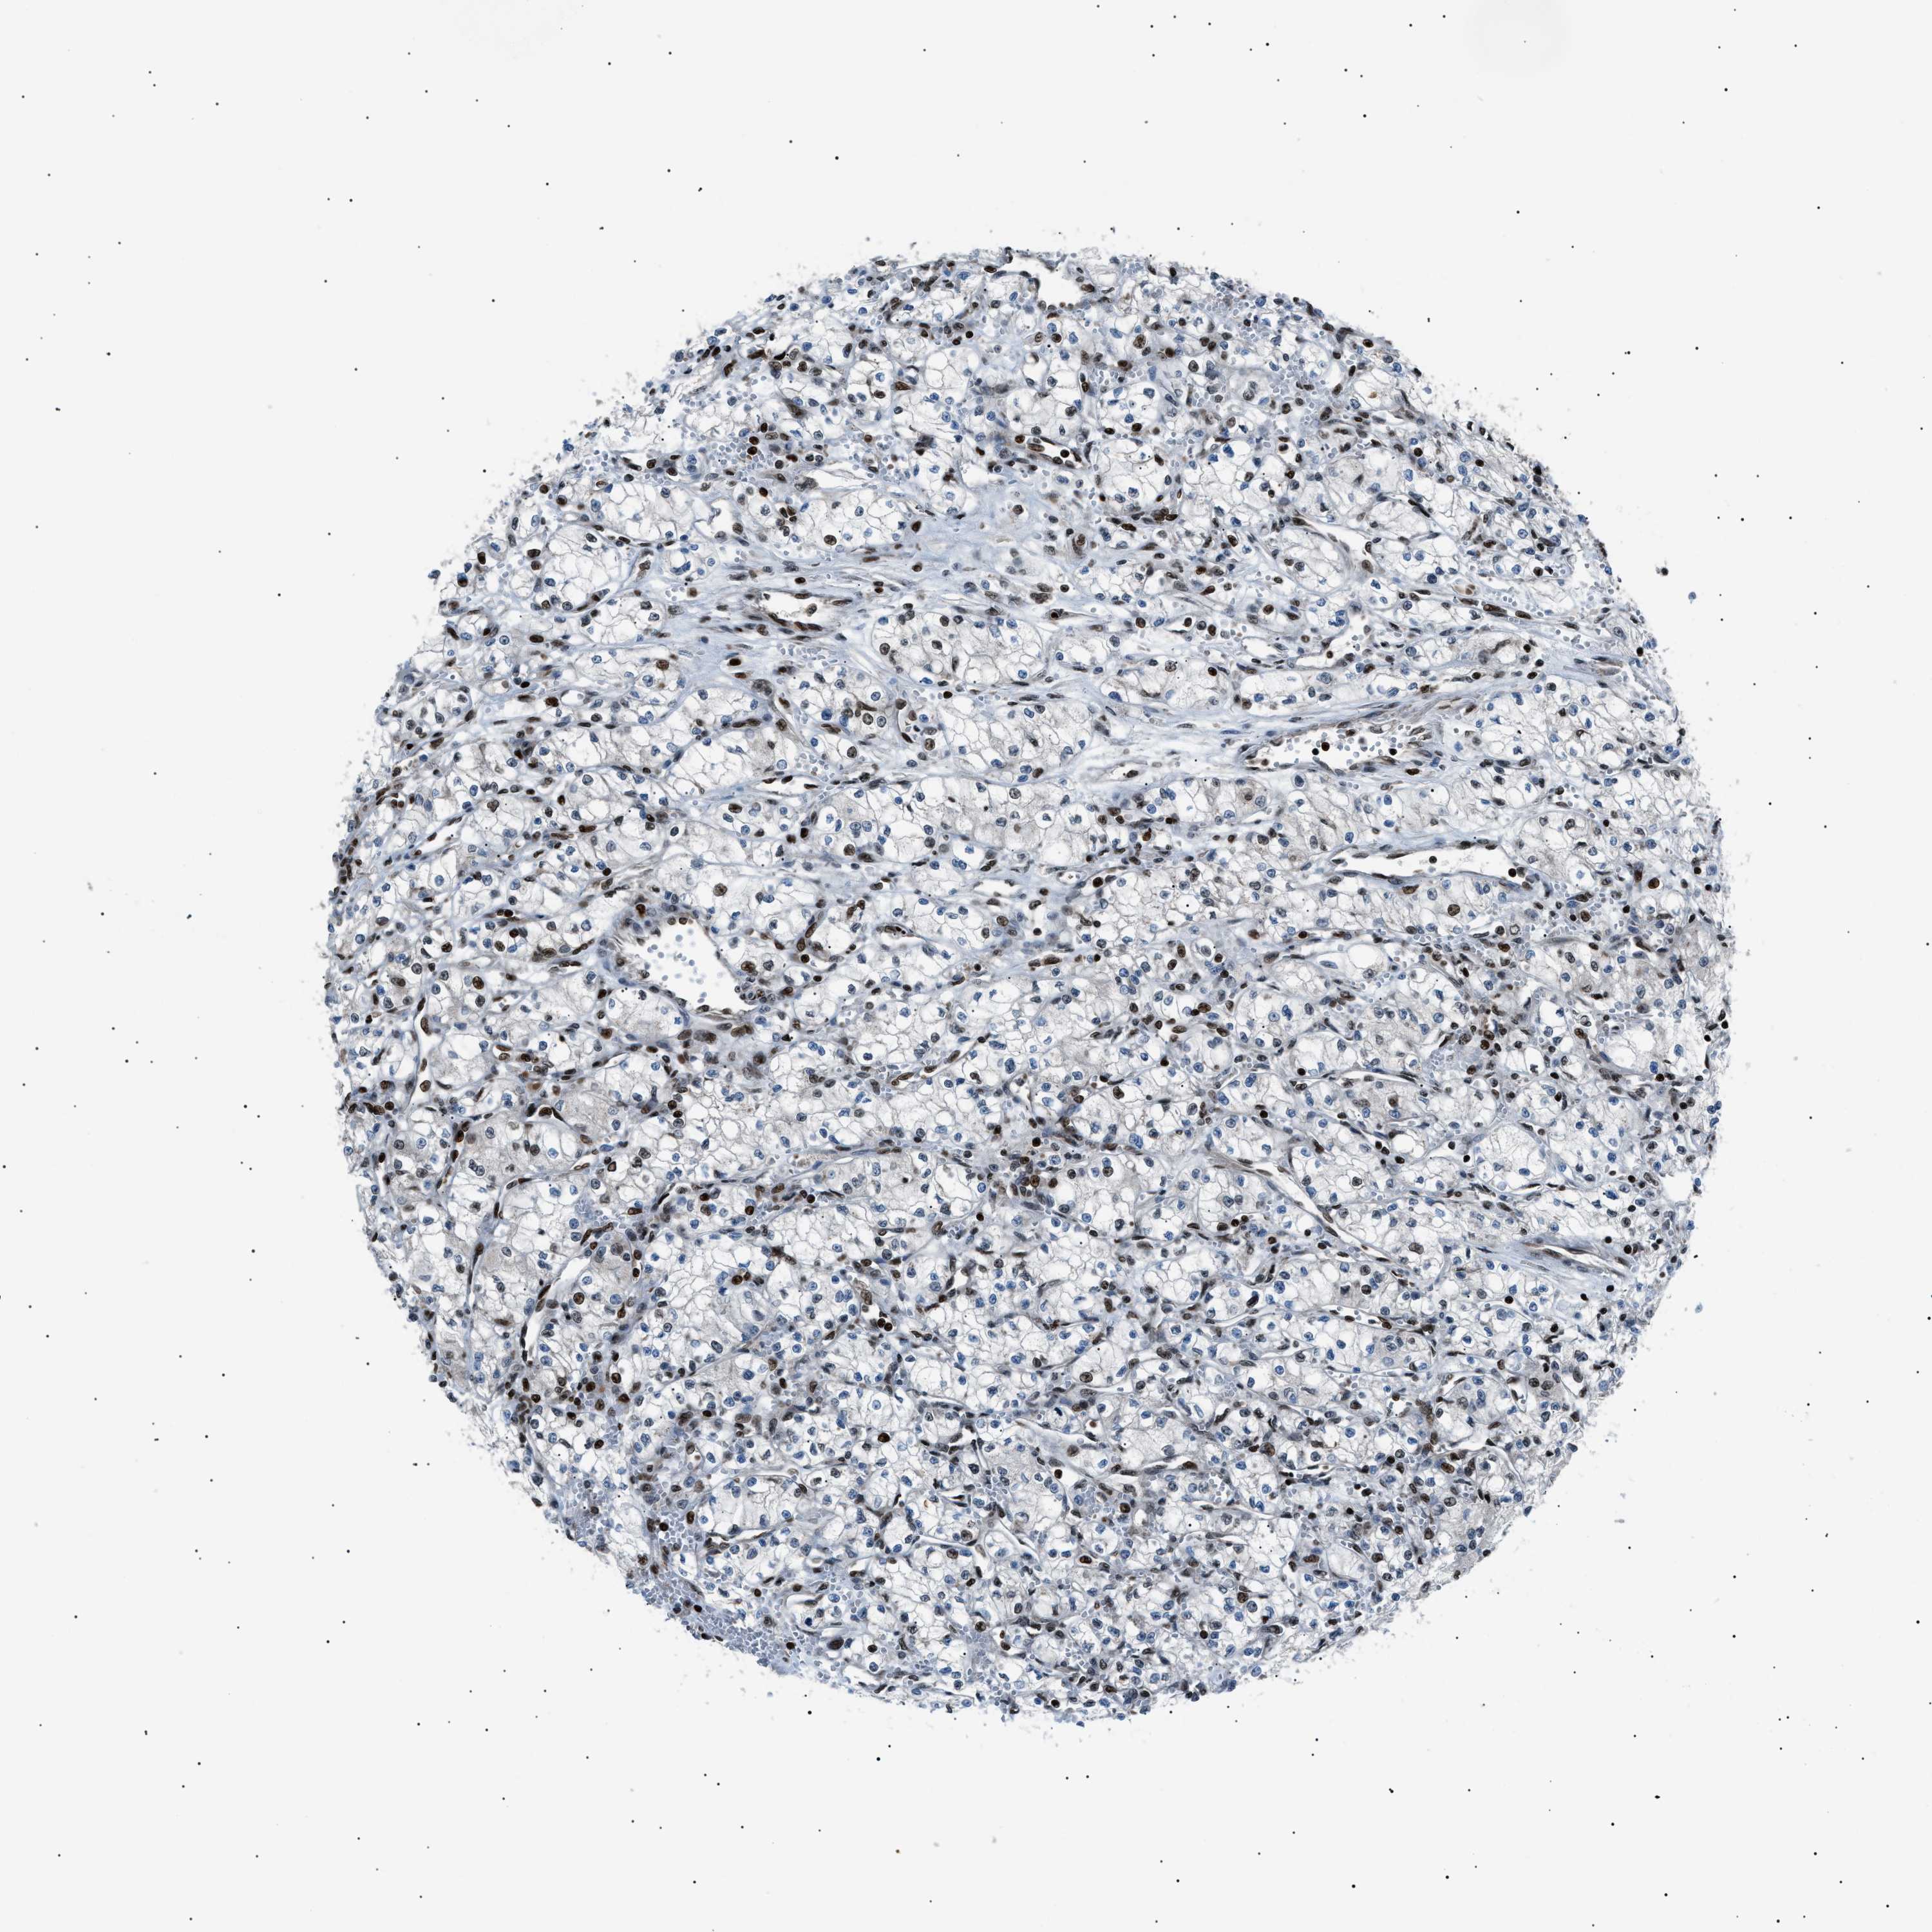

CANCER RENAL CANCER Show tissue menu

KICH TCGA KIRC TCGA KIRC VALIDATION KIRP TCGA PROTEIN RCC CPTAC PROTEIN EXPRESSION

KIDNEY CHROMOPHOBE (TCGA) - Interactive survival scatter ploti

The Survival Scatter plot shows the clinical status (i.e. dead or alive) for all individuals in the patient cohort, based on the same data that underlies the corresponding Kaplan-Meier plots. Patients that are alive at last time for follow-up are shown in blue and patients who have died during the study are shown in red.

The x-axis shows the expression levels (FPKM) of the investigated gene in the tumor tissue at the time of diagnosis. The y-axis shows the follow-up time after diagnosis (years). Both axes are complimented with kernel density curves demonstrating the data density over the axes. The top density plot shows the expression levels (FPKM) distribution among dead (red) and alive patients (blue). The right density plot shows the data density of the survived years of dead patients with high and low expression levels respectively, stratified using the cutoff indicated by the vertical dashed line through the Survival Scatter plot. This cutoff is automatically defined based on the FPKM cutoff that minimizes the p-score. The cutoff can be changed by dragging the vertical line or by entering a cutoff value in the square labeled "Current cut-off".

Under the Survival Scatter plot the p-score landscape (black curve; left axis) is shown together with dead median separation (red curve; right axis). Dead median separation is the difference in median mRNA expression between patients who have died with high and low expression, respectively. It is calculated as follows: median FPKM expression of dead patients with high expression - median FPKM expression of dead patients with low expression. This is intended to aid the user in visually exploring custom cutoffs and the associated p-scores and dead median separation.

Individual patient data is displayed and can be filtered by clicking on one or more of the category buttons on the top of the page. Categories describing expression level and patient information include: high, low, alive, dead, female, male and tumor stages. The scale of the x-axis can be toggled between linear and log-scale by clicking on the "x log" button. Mouse-over function shows TCGA ID, patient information and mRNA expression (FPKM) for each patient.

& Survival analysisi

Kaplan-Meier plots summarize results from analysis of correlation between mRNA expression level and patient survival. Patients were divided based on level of expression into one of the two groups "low" (under cut off) or "high" (over cut off). X-axis shows time for survival (years) and y-axis shows the probability of survival, where 1.0 corresponds to 100 percent.

PRKX is not prognostic in Kidney Chromophobe (TCGA)